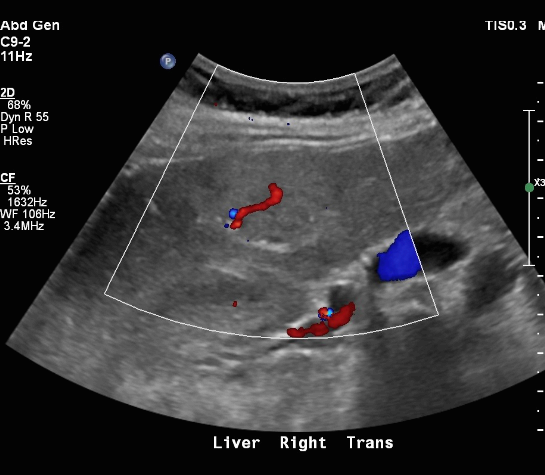

FNH (Focal Nodular hyperplasia) US finding

- spokewheel vascularity

- iso-hyperechoic mass